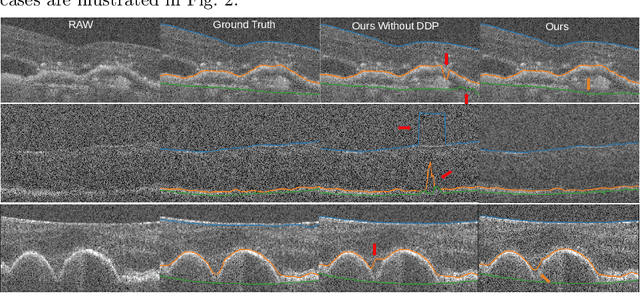

Abstract:Segmentation of multiple surfaces in medical images is a challenging problem, further complicated by the frequent presence of weak boundary and mutual influence between adjacent objects. The traditional graph-based optimal surface segmentation method has proven its effectiveness with its ability of capturing various surface priors in a uniform graph model. However, its efficacy heavily relies on handcrafted features that are used to define the surface cost for the "goodness" of a surface. Recently, deep learning (DL) is emerging as powerful tools for medical image segmentation thanks to its superior feature learning capability. Unfortunately, due to the scarcity of training data in medical imaging, it is nontrivial for DL networks to implicitly learn the global structure of the target surfaces, including surface interactions. In this work, we propose to parameterize the surface cost functions in the graph model and leverage DL to learn those parameters. The multiple optimal surfaces are then simultaneously detected by minimizing the total surface cost while explicitly enforcing the mutual surface interaction constraints. The optimization problem is solved by the primal-dual Internal Point Method, which can be implemented by a layer of neural networks, enabling efficient end-to-end training of the whole network. Experiments on Spectral Domain Optical Coherence Tomography (SD-OCT) retinal layer segmentation and Intravascular Ultrasound (IVUS) vessel wall segmentation demonstrated very promising results. All source code is public to facilitate further research at this direction.